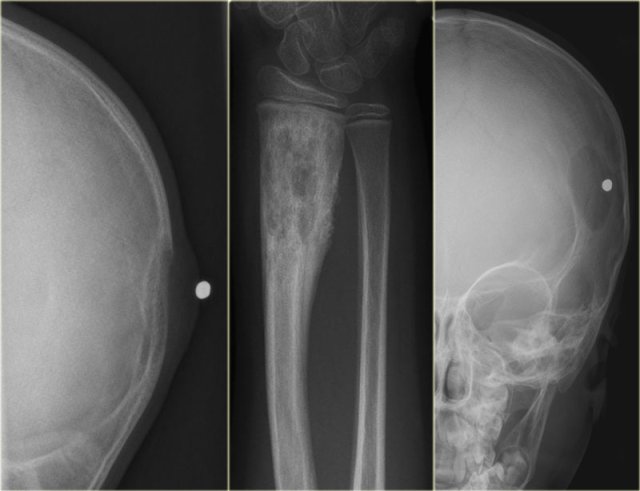

- left

Osteolytic lesion arising from the neurocranium with associated soft tissue swelling. - middle

Mixed lytic-sclerotic lesion, not well-defined with solid periosteal reaction. - right

Sharply defined osteolytic lesion of the skull. There is no 'button sequestrum', which is more or less pathognomonic.

Discriminator:

- Must be under age 30.